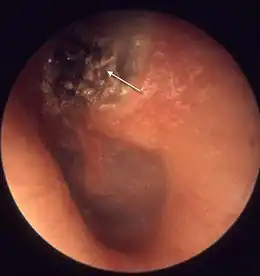

Il se fait par visualisation du conduit auditif et du tympan (otoscopie). Il se manifeste par la présence d'une excroissance squameuse, le plus souvent à la partie postéro supérieure du tympan[7]. Le scanner crânien permet de visualiser l'extension et les éventuelles destructions osseuses.L'histopathologie post-opératoire est indispensable pour confirmer la nature de la lésion et celles qui lui sont associées.